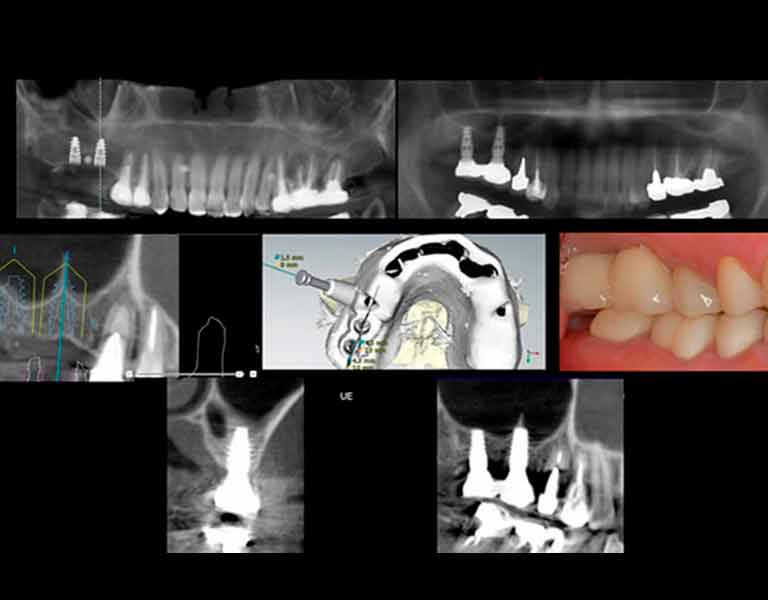

そして、インプラント治療のナビゲーションシステムと言えるシステムが「デジタルインプラント」です。

本書において、この「デジタルインプラント」とはどのようなものか?

そして今までのインプラント治療とどう違うのか?をお話していきたいと思います。